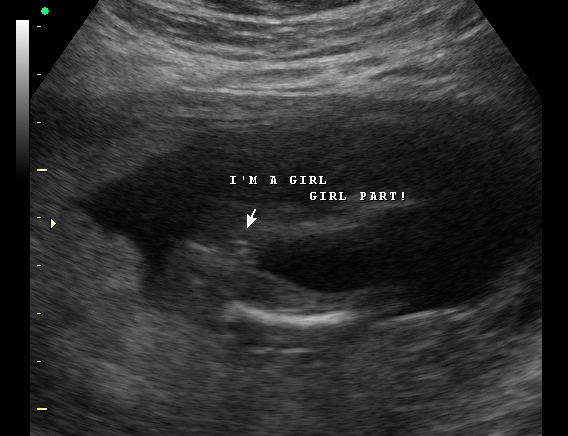

After only having boy ultrasounds I am still in denial that our last little one is indeed a little princess. I want to gradually start buying a few things since I have to start over from scratch so I just need some reassurance. What do you ladies think? Ultrasound was done at 17 weeks

• Remember that the ultrasound tech had more views then this one picture so with that based off this one picture it looks like a girl but I would really trust the ultrasound tech and if your not sure yet you can always by gender neutral until your more comfortable.

• She was sure it was a girl, the same lady did our boy ultrasound reveal last time. I think I am just in a little denial.....:) it is our last little one and lo and behold a little girl.

• I agree that it looks like a girl.

• That's a girl

• It definitely doesn't look like the 18 week ultrasound of my boy, congratulations!

• Looks girl to me

• Looks like a girl to me too!

• Thanks Ladies....I am so hoping she was right. She was right with my baby boy last time but ppl say that girls are a little trickier.